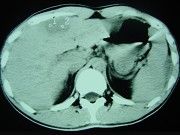

- 单项选择题男,35岁, 病人低热、消瘦、乏力,左右季肋区疼痛, CT扫描如图所示,请选择最佳诊断 ( )

A、肝海绵状血管瘤、腹腔脓肿

B、肝脏及腹腔转移瘤

C、肝脓肿、腹腔脓肿

D、肝癌、腹腔转移

E、肝结核、腹腔结核